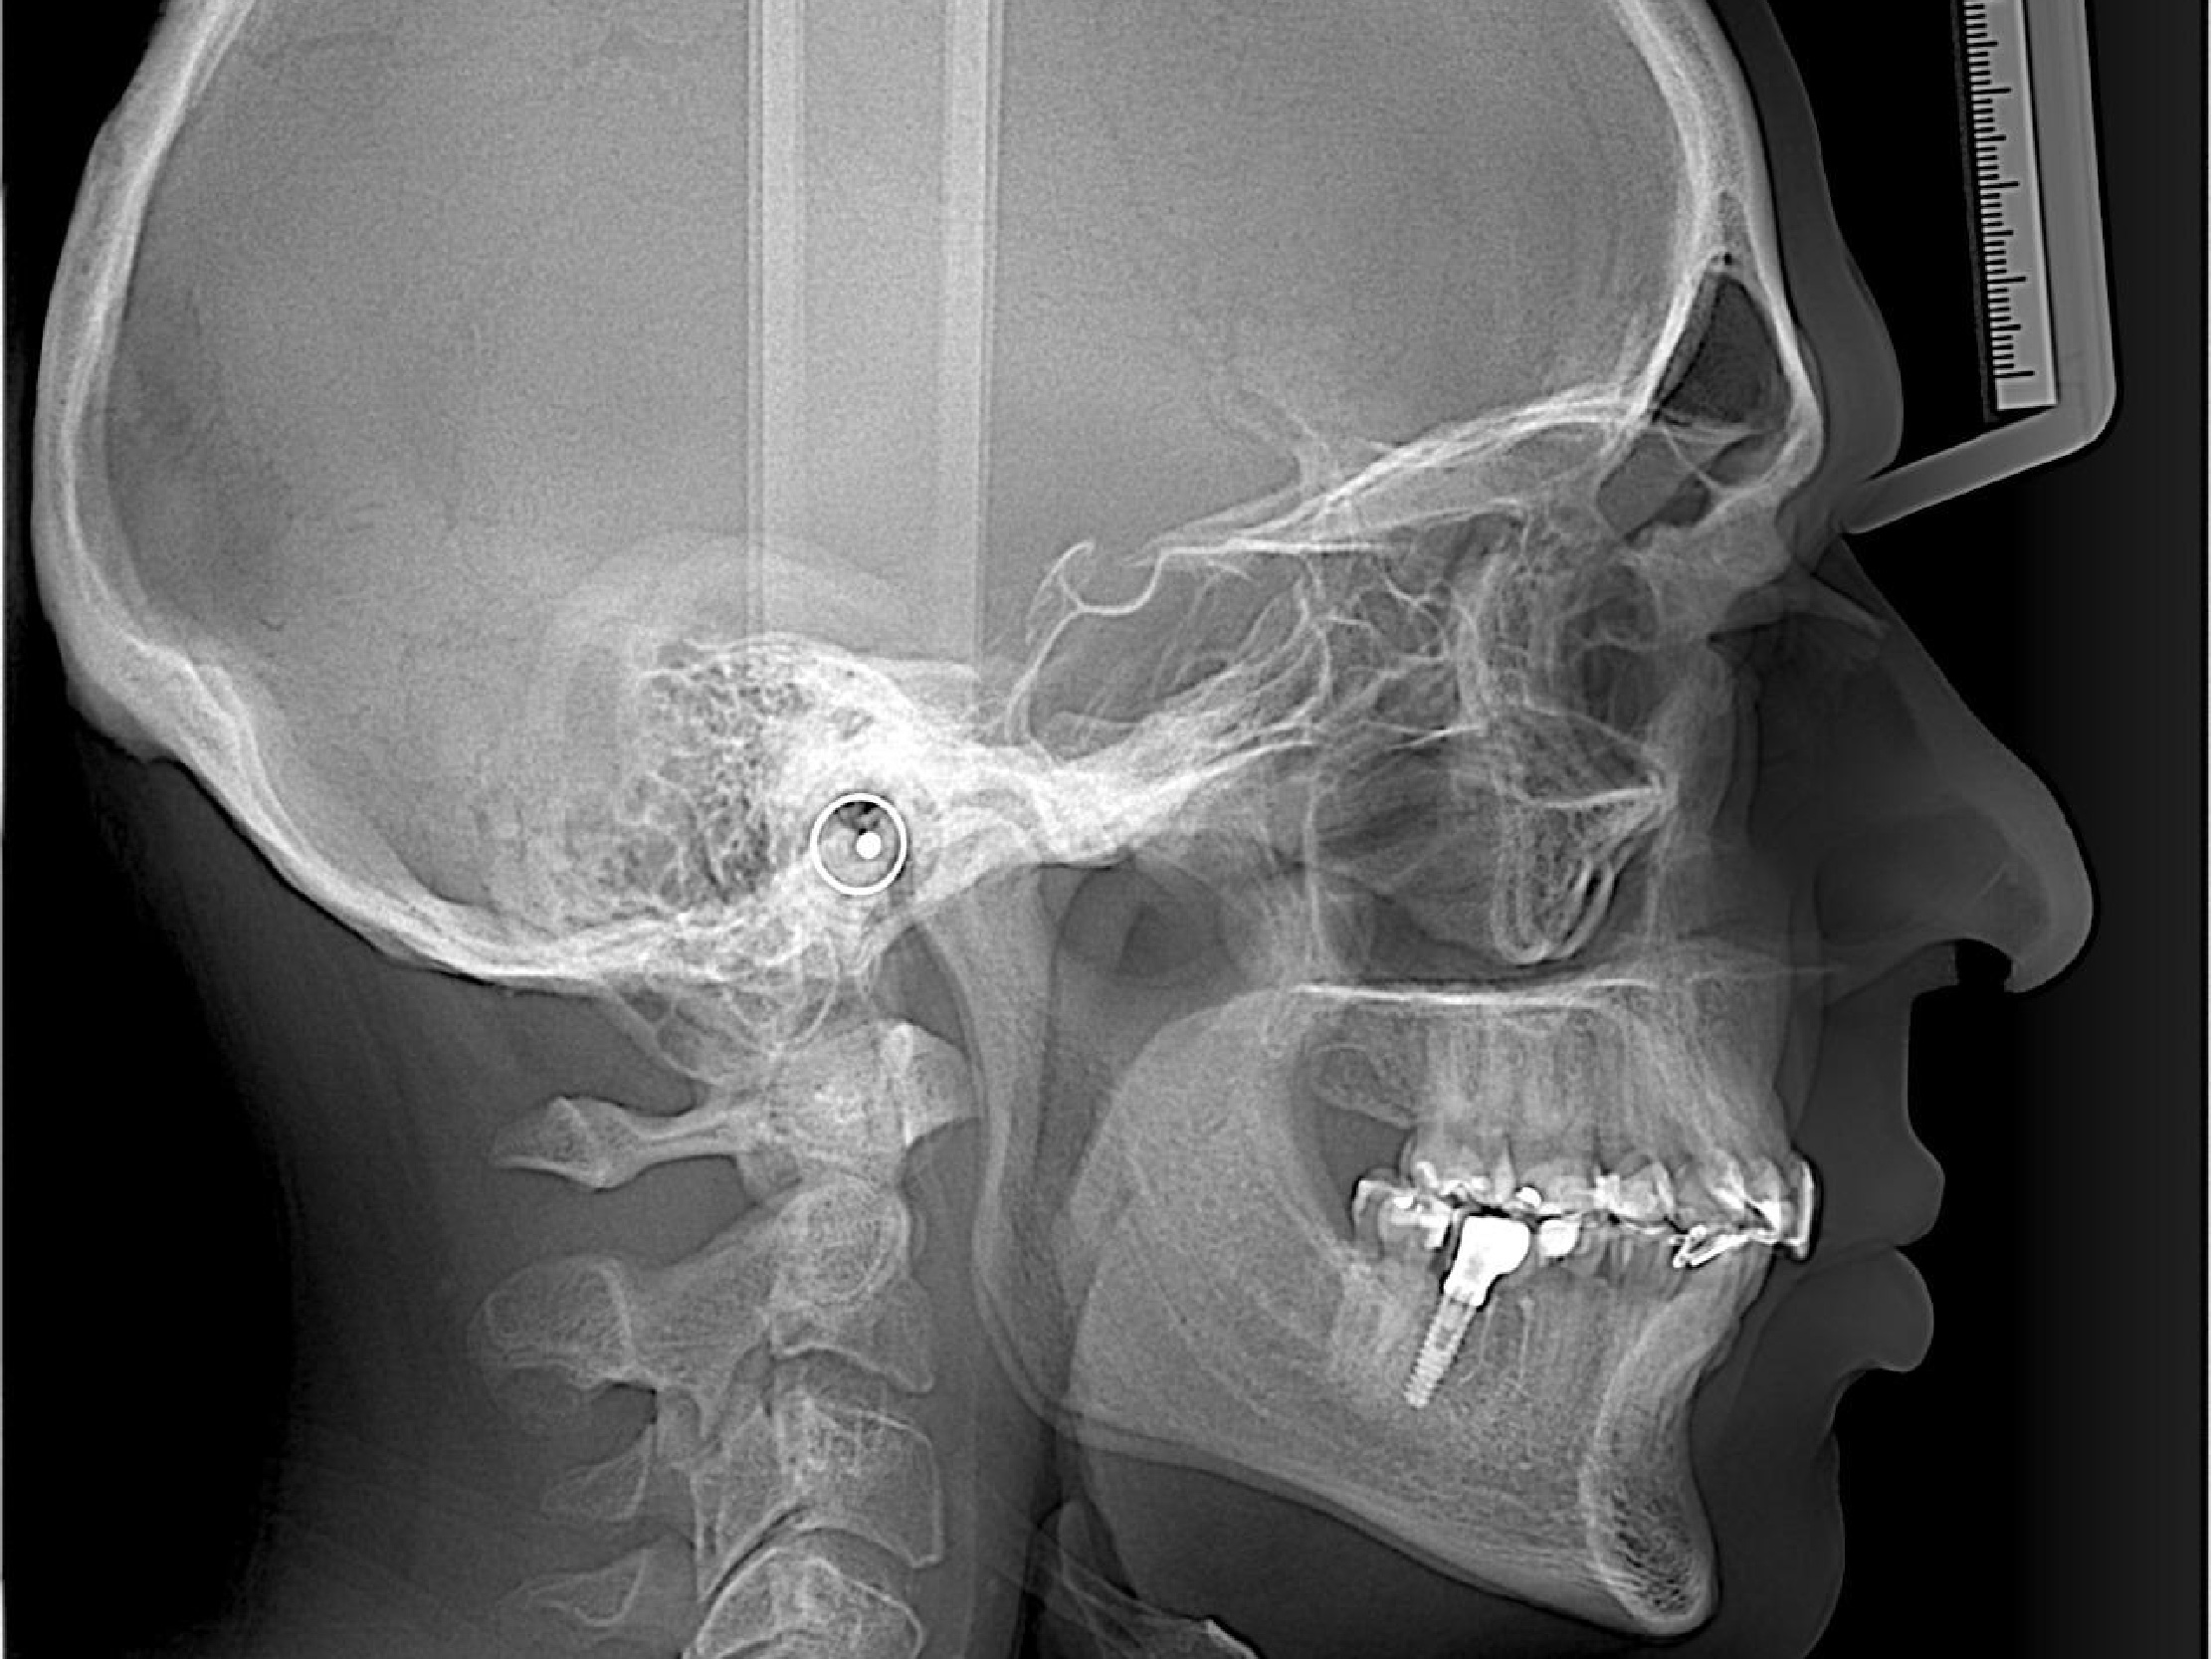

• Vista de Cefalometria Lateral.

• Trazado Automático Identifica puntos en segundos.

Trazado Cefalométrico